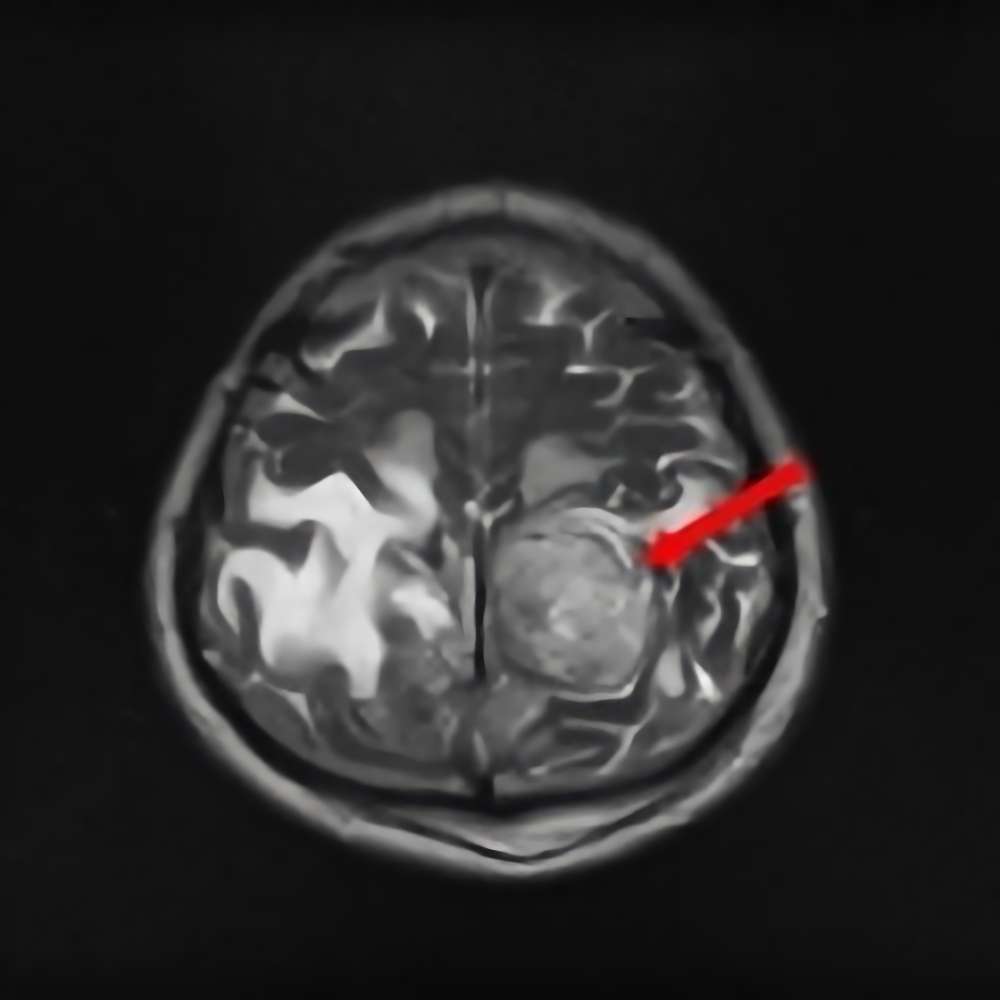

'15年6月

50代

側頭葉膠芽腫

No.’15_68 手術前1

No.’15_68 摘出 前

No.’15_68 摘出 後